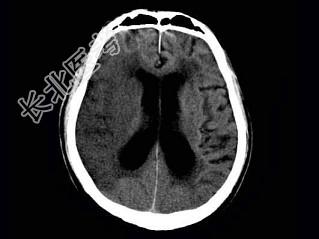

- 单项选择题女,75岁, 突发左侧肢体无力,嘴角歪斜, 言语表达不清,CT如图, 最可能的诊断是 ( )

A、右侧颞顶枕叶梗死

B、星形细胞瘤

C、脑脓肿

D、少枝胶质细胞瘤

E、脑囊肿